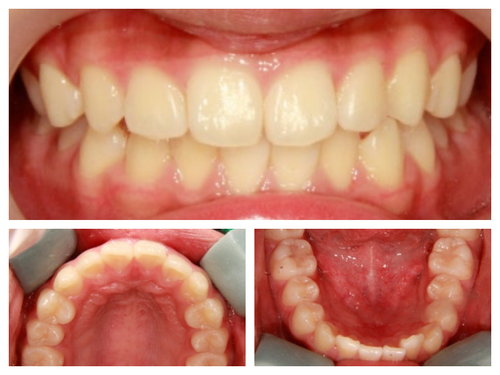

사실 골격적인 비대칭이 심해서 교정이 끝나도 비대칭이 남겠지만 돌출이 개선되면 훨씬 예뻐질것이기에 과감히 발치를 하고 좌,우 최대한 중심선을 맞추면서 교정을 끝낸 케이스

입이 들어가서 예뻐진 것 뿐아니라 사진을 찍으면 두드러지던 비대칭도 많이 줄어들었다.

이제 자신있게 무대에서도 활짝 웃고 사진 찍는 것도 두렵지 않다고^^

돌출입 교정을 통해 입술의 모습이 많이 바뀌니 잇몸 노출량도 훨씬 줄어서 웃을때 신경이 더 쓰인다고...

무대를 서는 아이들이라 교정하는 내내 신경이 많이 쓰였던 케이스들인데 나도 환자도 보호자도 모두 만족할 수 있어서 다행이었다...